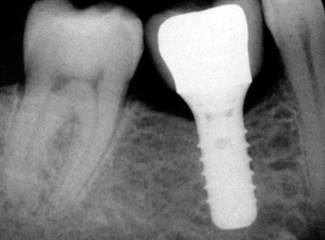

PLACEMENT OF DENTAL IMPALNT

OSTEOINTEGRATE DENTAL IMPLANT SURGERY